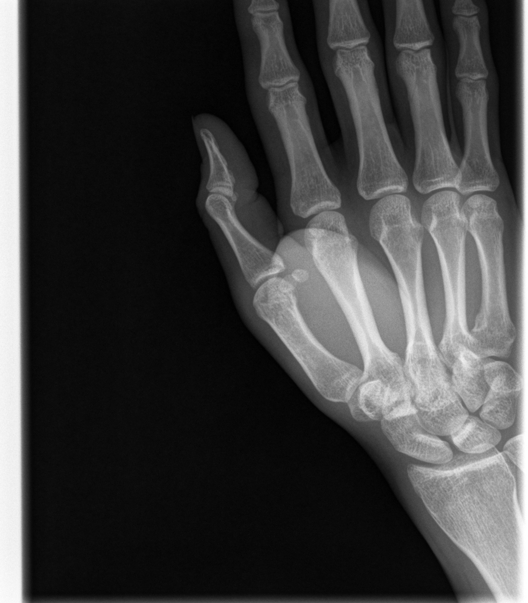

A little part of my bone that evidently chipped away from the main thumb.

It turned out that I had a small chip in the bone, though it wasn't a huge deal. After a couple of days of keeping it compressed and icing it, the swelling was gone. It only took a couple of weeks to resume full use of the hand.